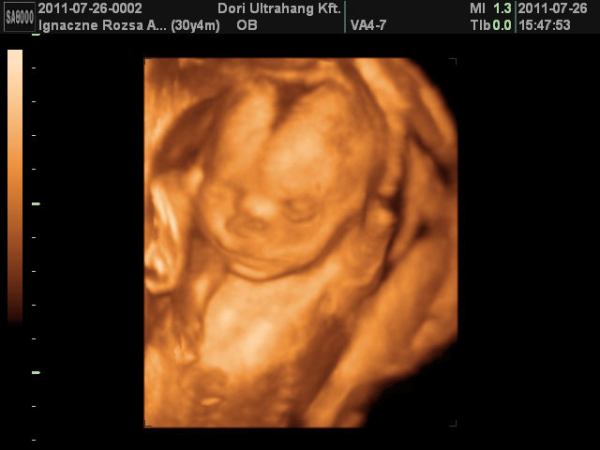

Mi jól vagyunk tegnap voltunk UH-n dobok malyd képet.

Milán sajna beteg volt ahogy már írtam, és szép pöttyeink is lettek.